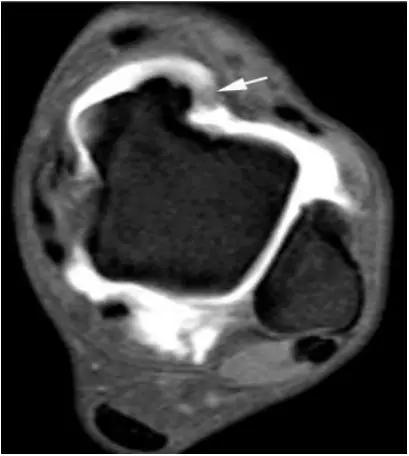

5.后内侧撞击综合症:

影像学表现为距骨胫骨间肌腱及趾长屈肌腱水肿、增厚,内踝及距骨后内侧骨赘形成。

轴位示意图示后内侧撞击综合征:M:内踝;L:外踝;TP:胫后肌腱;FDL:趾长屈肌腱;Talus:距骨。短箭:距骨胫骨间肌腱深层纤维;箭头:距骨胫骨间肌腱后部纤维。

X线平片示胫骨后部骨赘形成,MR质子像黑箭示胫骨内后侧骨赘形成,白箭示内后侧软组织增厚, 白箭头:胫后肌腱;黑箭头:趾长屈肌腱